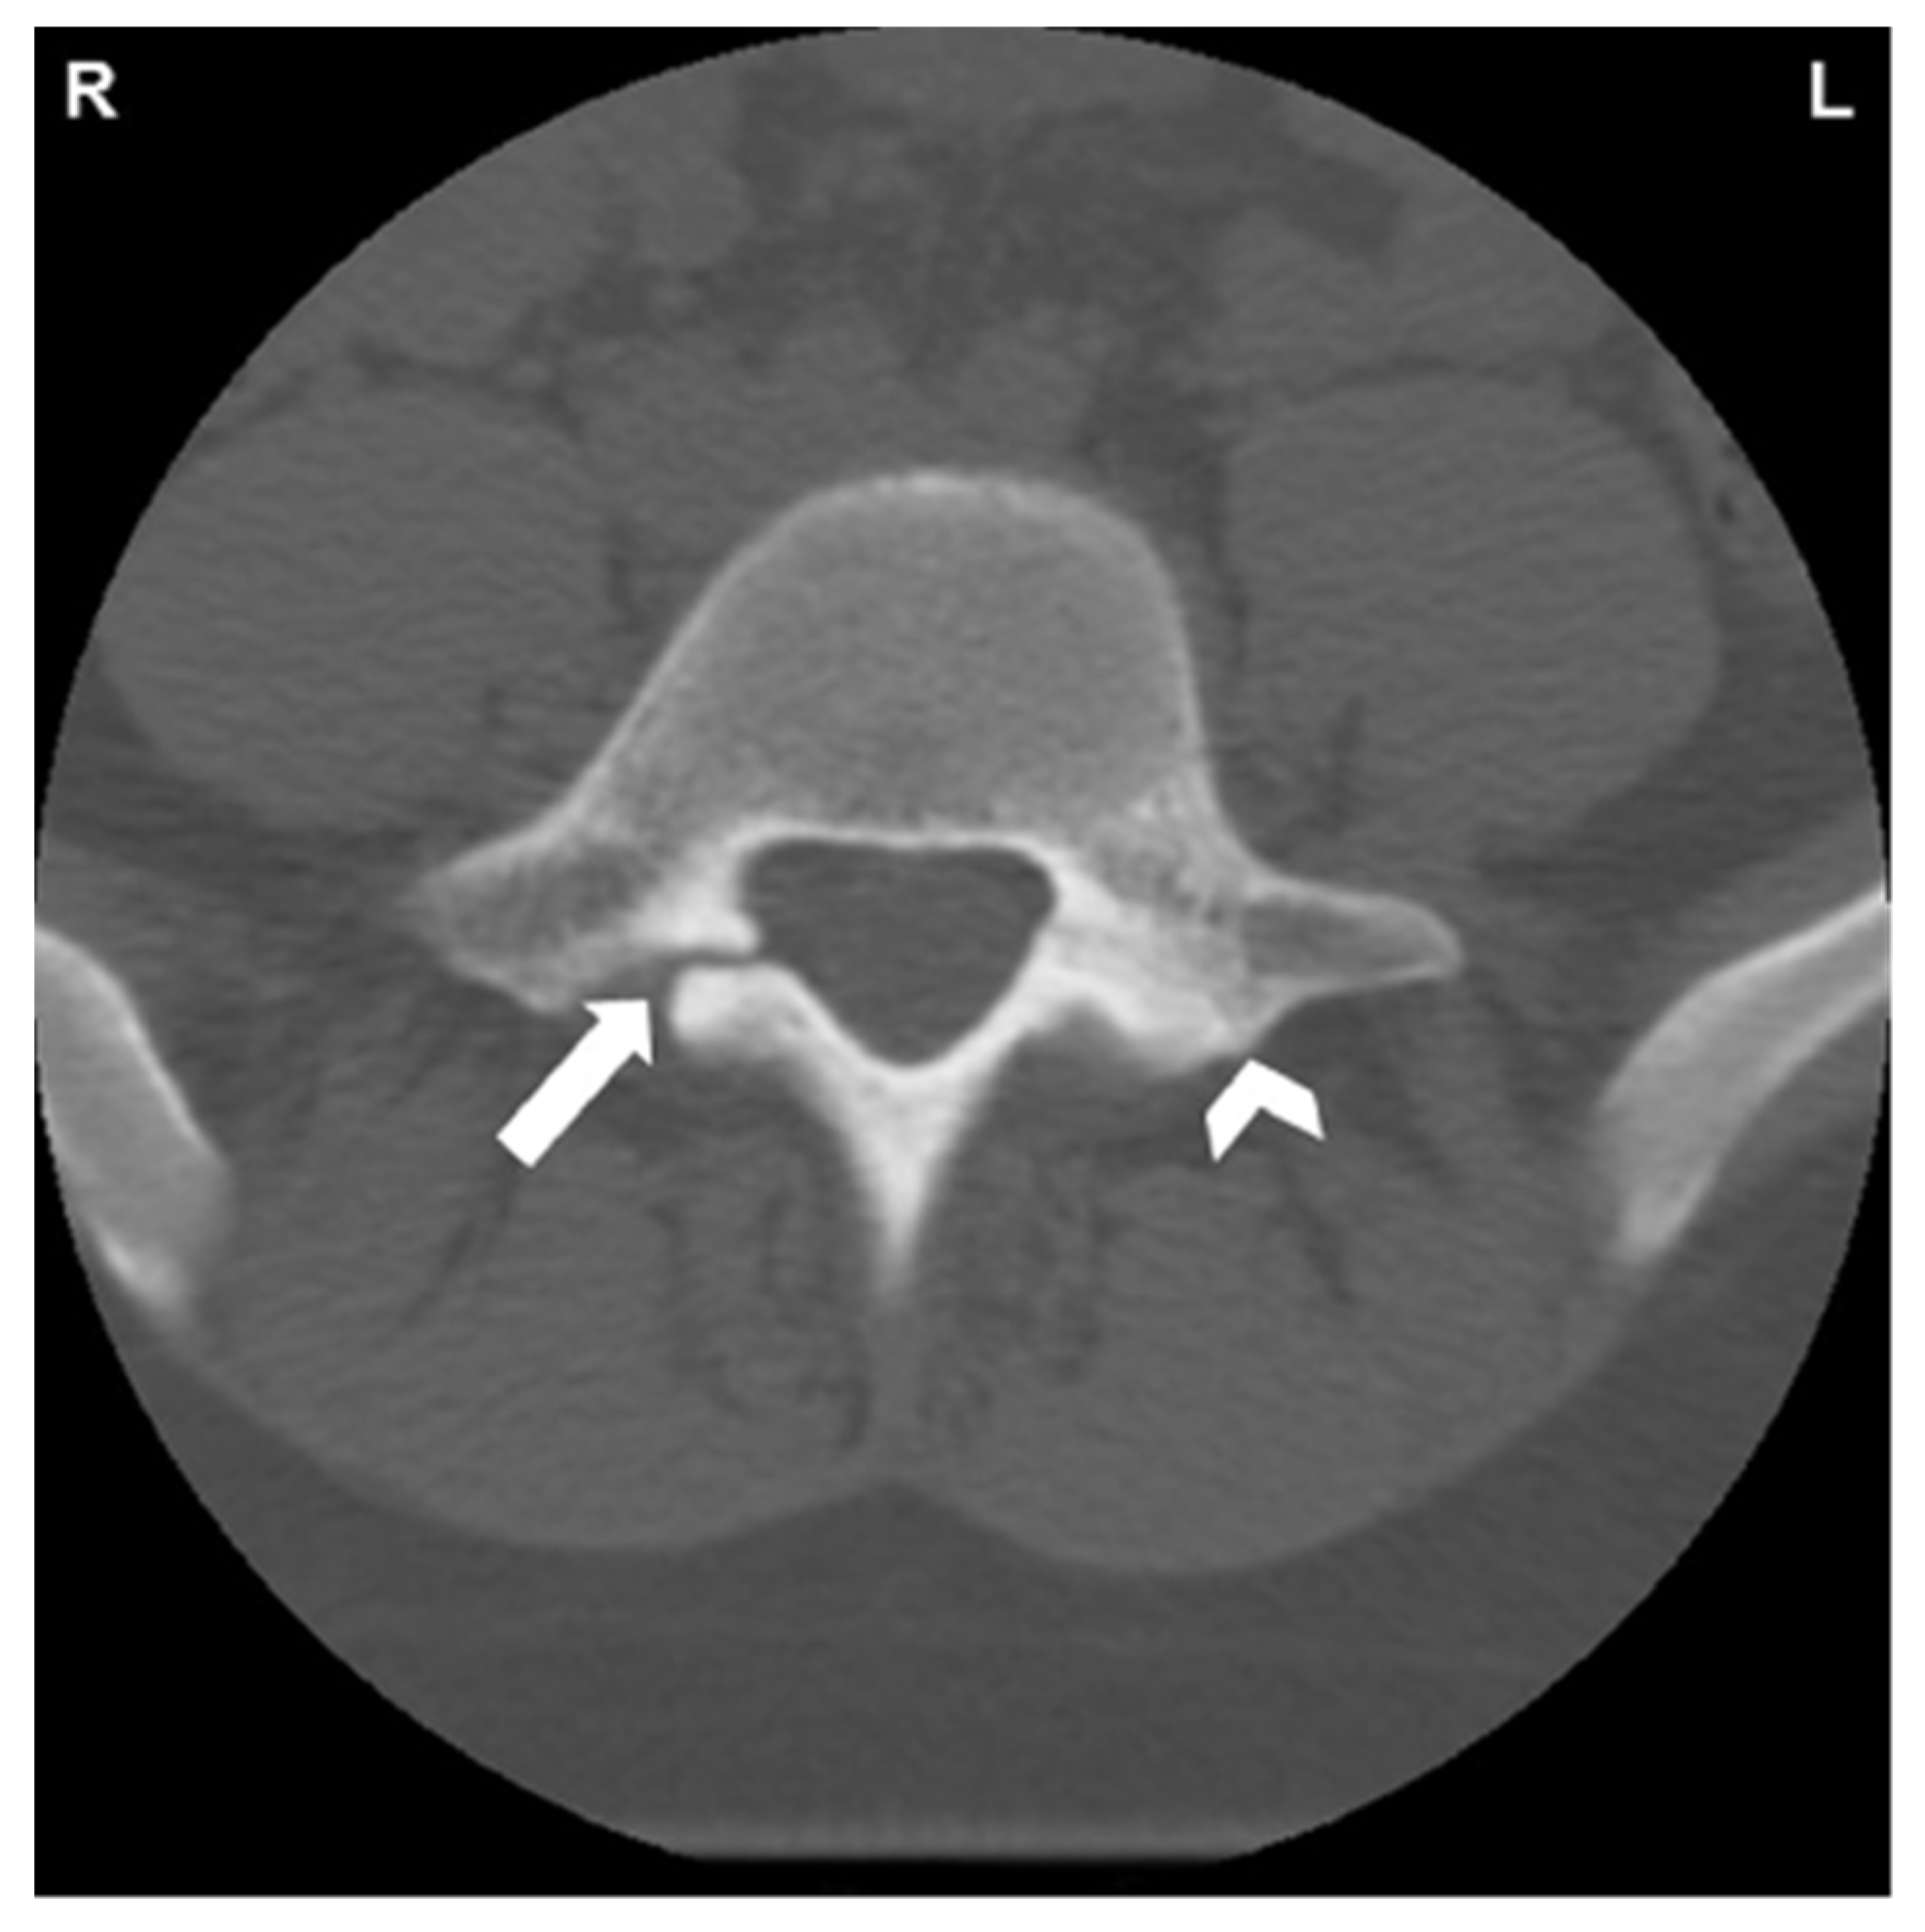

1.5. Imaging

- Leone, A.; Cianfoni, A.; Cerase, A.; Magarelli, N.; Bonomo, L. Lumbar spondylolysis: A review. Skelet. Radiol. 2011, 40, 683–700. [Google Scholar] [CrossRef] [PubMed]

- Fayed, I.; Conte, A.G.; Voyadzis, J.-M. Success and failure of percutaneous minimally invasive direct pars repair: Analysis of fracture morphology. World Neurosurg. 2019, 126, 181–188. [Google Scholar] [CrossRef]